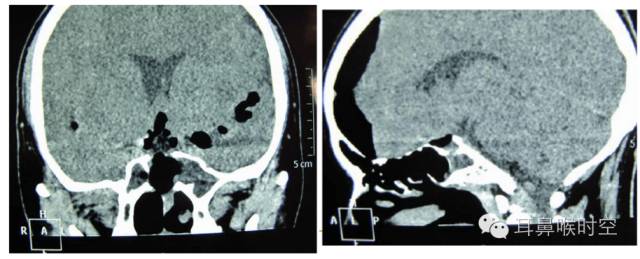

影像学检查:MRI

T2WI因CSF信号强化而确诊CSF漏

显示漏口周围硬脑膜下积液

显示筛窦或上颌窦积液征

显示脑膜脑组织膨出

颅内脑脊液高信号影与含脑脊液的鼻腔或鼻窦高信号影之间有线状高信号影连接,线状高信号影的直径为漏口大小

现广泛使用的MRI 水成像技术,定位漏口准确

自发性脑脊液鼻漏

左:筛顶漏伴有鼻息肉 右:筛板漏